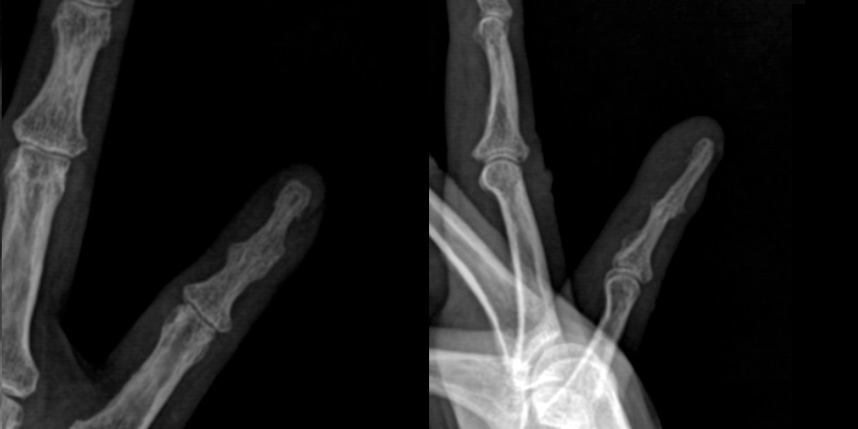

손가락의 관절염은 크게 류마티스성 관절염과 퇴행성 관절염으로 나뉩니다.

두 질환은 근본적으로 발생 원인이 다르며 퇴행성 관절염은 과도한 사용이 원인이 되어 관절이 닳게 되는 퇴행성 질환입니다.

주로 류마티스 관절염은 근위지절을 침범하며 다른 내과적인 증상이 동반할 수 있으며 염증 수치가 올라가고,

퇴행성 관절염은 원위지절을 주로 침범하여 손가락 마디가 두꺼워 지게 됩니다.

초기 증상으로는, 손가락 관절의 통증과 뻣뻣함이 있으며, 관절 주변이 자주 붓고 열감이 느껴질 수 있습니다.

시간이 지남에 따라 다음과 같은 증상이 나타날 수 있습니다.

관절의 변형

관절 운동 제한